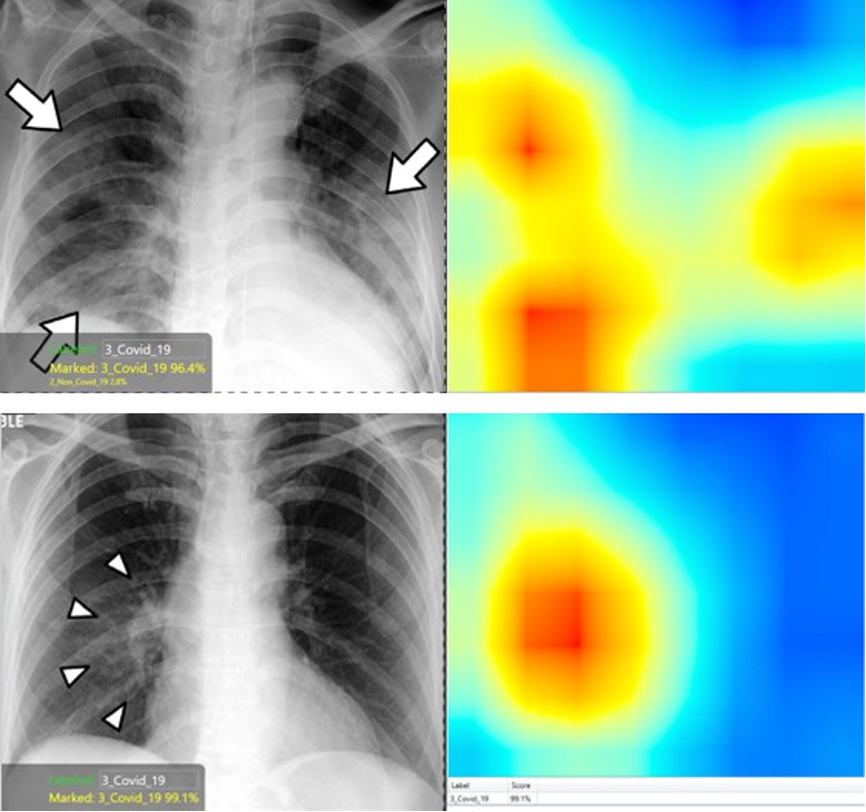

在这种背景下,康耐视VisionPro Deep Learning软件提供了有用的热图功能,其突出显示了图像中对于分类非常重要的区域。黄色到红色区域很重要,而绿色到蓝色区域对于决策算法并不重要。

在现实世界中,这种热图功能使该工具不仅可以为潜在的诊断提供建议(即Covid-19阳性或阴性),还可以识别出检测到相应疾病症状的区域。这一点很重要,因为它可以帮助放射科医师在图像的特定区域进行归零校正,以使他们能够验证或推翻AI诊断,从而防止该软件工具因错误的原因无法做出正确的决策。